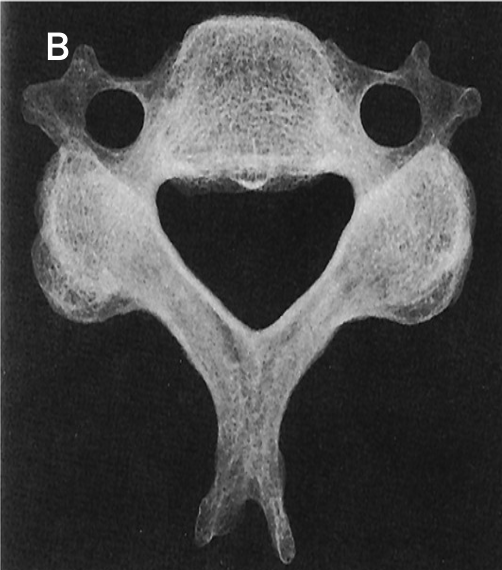

What type of bone is figure B? How many vertebrae are there in the spinal column?

A

Irregular bones

26 (includes sacrum & coccyx)